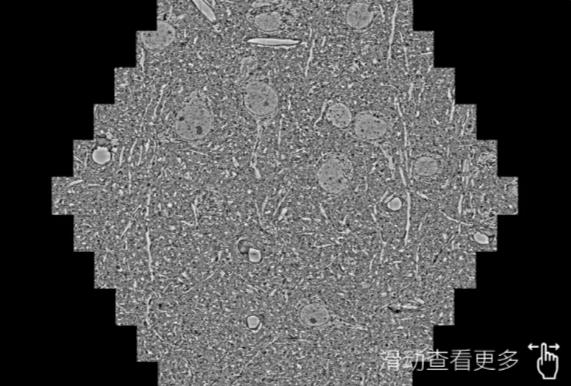

鼠脑切片。左图使用永川蔡司永川扫描电镜MultiSEM706对165μmx143pm面积区域成像,耗时仅需1.5秒。右图为鼠脑切片中30μm区域放大效果。样品由芝加哥大学B.Kasthuri提供。

使用蔡司高速永川扫描电镜MultiSEM对1mm²人脑皮层组织进行高分辨成像,并对其中的各种细胞结构进行三维重构分析。左图展示了2x3mm²组织平面中锥体神经元的三维重构效果。右图显示了局部体积神经元三维重构。图像由哈佛大学chtman实验室提供,渲染图由D. Berger 制作。